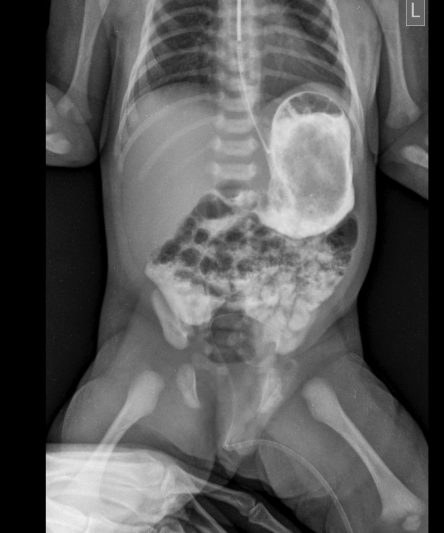

Microskan with Ultra high frequency can take the Lateral Lumbar Spine image of a 90 kg Patient with the correct image receptor

Microskan is the lightest mobile X-ray unit available